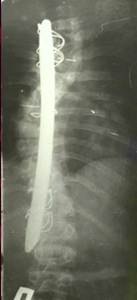

Динамический корректор. Результат на 2-е сутки после операции

В дальнейшем А.А. Гайдуков разработал и создал эндокорректор с деротационными скобами с фиксацией в блоках креплений на нескольких уровнях. Данный эндокорректор позволил эффективно на 60-100% корригировать деформацию при сколиозе III-IV степени. Но тяжелая многочасовая операция, травматичность вмешательства, проволочная фиксация и нередкие неврологические осложнения ограничивали применение данной методики.

Результат коррекции сколиотической деформации эндокорректором с деротационными скобами